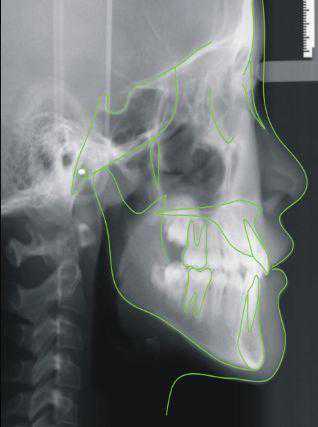

牙弓对脸型的影响↓

大众的审美都认为中型面孔为最好看的面孔,两侧对称,协调自然,并各自与个体的面型、牙型相一致,这是专业正畸医生需要全面评估的。这不仅能保持牙在颌骨上的稳固性,以便发挥其最大的咀嚼功能,并能保护牙周组织的健康及支持颌面部的软组织,使颜面外形丰满美观。

正畸不单纯只是把窄的扩宽,宽的变窄这么简单,还需要根据你的面型设计出最适合你的方案。

专业的正畸医生就像建筑师一样,建筑风格大小和街道宽窄匹配,注意留白。牙齿排列也要考虑颌骨和肌肉软组织匹配,发挥局部最大的优势,使整体效果看上去更协调。